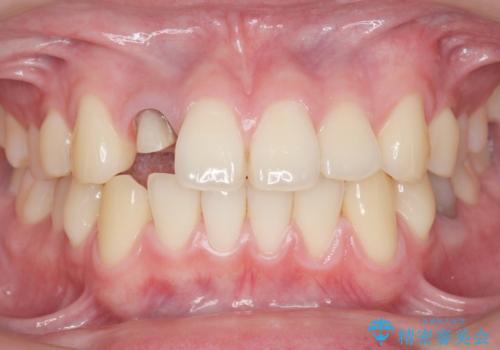

- 他院で入れたセラミッククラウンの色が気に入らないことを主訴に来院された患者様です。

高校生の時に部活で前歯をぶつけて神経が死んでしまい、歯が黒く変色したためセラミッククラウンで治療したとのことでした。

精査したところ、透過性のあるセラミッククラウンで治療されており、内側の黒い土台が透けてクラウンが黒ずんで見えていました。

失活(神経が死んでしまっていること)により黒くなった歯根が透けて歯ぐきも黒ずんで見えるため、歯肉移植の手術も提案しましたが、そこまでは気にならないとご希望されませんでした。